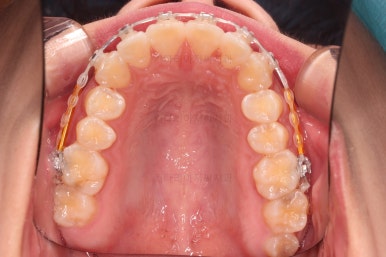

초진 시 입안의 모습입니다.

어금니 쪽은 약간 삐뚤긴 하지만 꼭 교정해야 할 정도는 아니고, 불편감 없이 비교적 잘 맞물리는 상태였습니다.

다만, 앞니ㅉㄱ이 공간이 부족해서 중간 치아들이 많이 회전되어있는데, 이를 환자분들의 표현에 따르면 "나비치아" 라고 부릅니다.

위아래 중간 앞니가 모두 나비치아처럼 되어있고요.

윗니가 아랫니보다 앞쪽으로 나와 있는 모습에 아래앞니가 윗니쪽으로 깊숙이 올라간 "과개교합" 양상을 보였습니다.